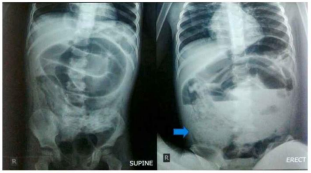

Figura A: Raio-X abdominal evidenciando alças dilatadas do intestino delgado.